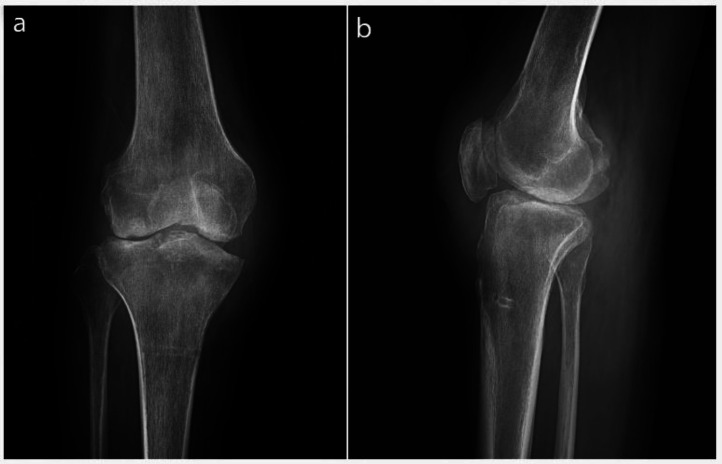

Neglected knee dislocations are rare and challenging orthopedic injuries. We report using a traction pin to treat a neglected knee dislocation and a concurrent infection. Following the primary reduction with extensive soft-tissue release, a proximal tibial traction pin was used to obtain complete reduction via traction weight change.‎ No ligamentous repair was done for the patient. The patient's one-year follow-up showed an acceptable radiographic reduction supported by satisfactory clinical outcomes. In conclusion, the proximal tibial traction pin could be a good alternative for treating neglected knee dislocations. It makes future knee replacements more practical, a significant concern in such patients. Meanwhile, it is much more affordable than the other available techniques.